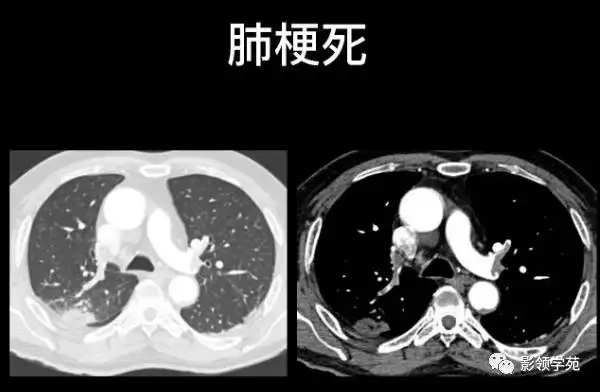

肺栓塞的影像诊断与鉴别诊断